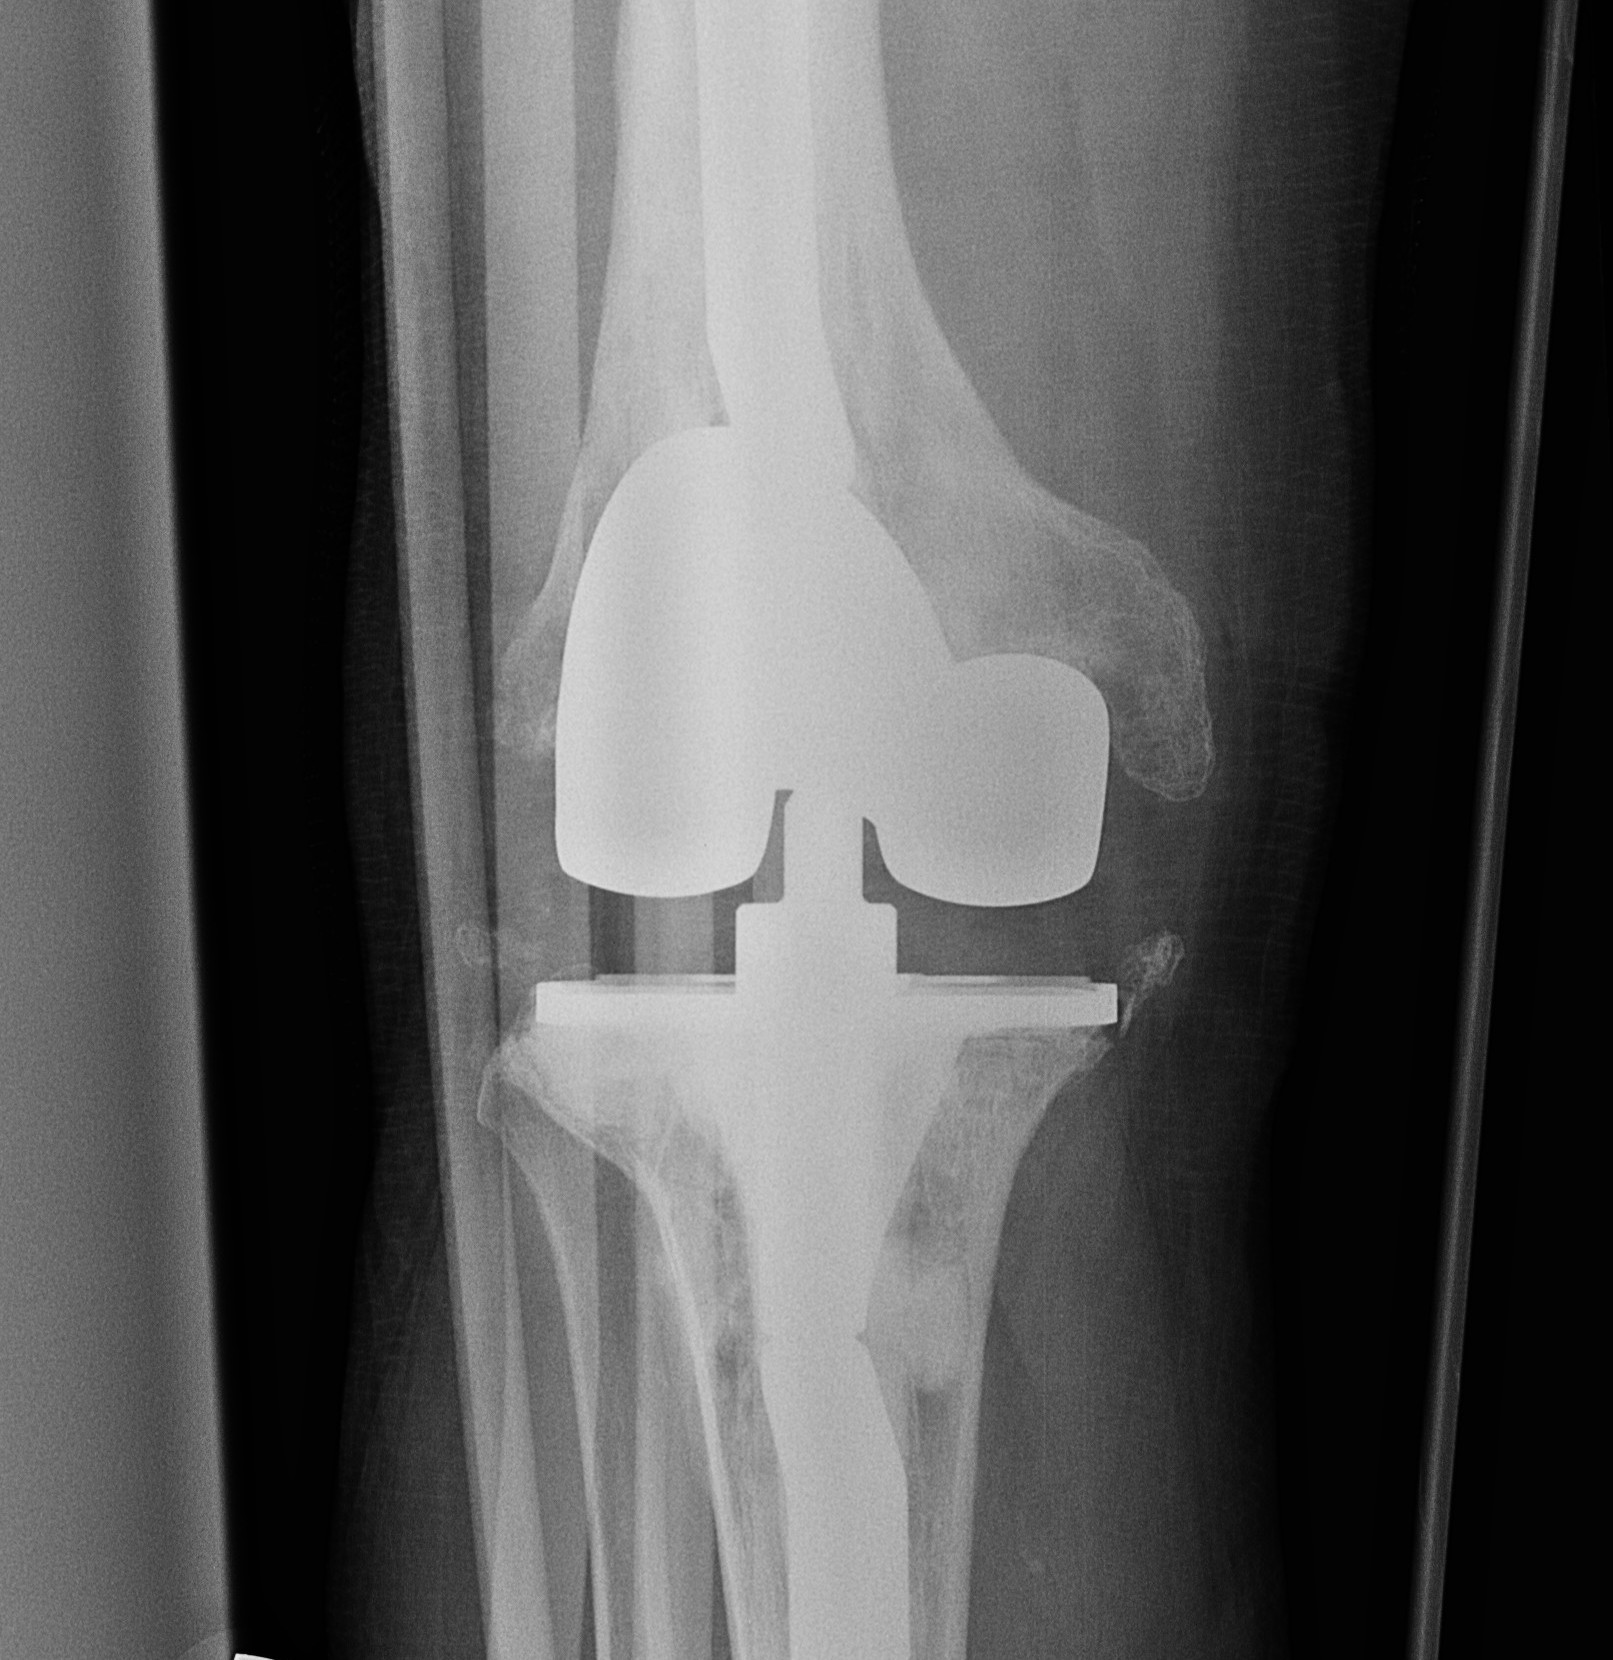

Removal of components

Remove poly

- implant specific tools

Careful removal implants to minimise bone loss

- thin, flexible osteotomes, micro-sagittal saw

- gigli saw

- can cut metal with carbide burr

Cemented femur / tibia

- separate at cement-implant interface

- remove cement later

Uncemented femur / tibia

- rarely have to cut base plate from keel (carbide burr)

- can perform TT osteotomy

- stacked osteotomes